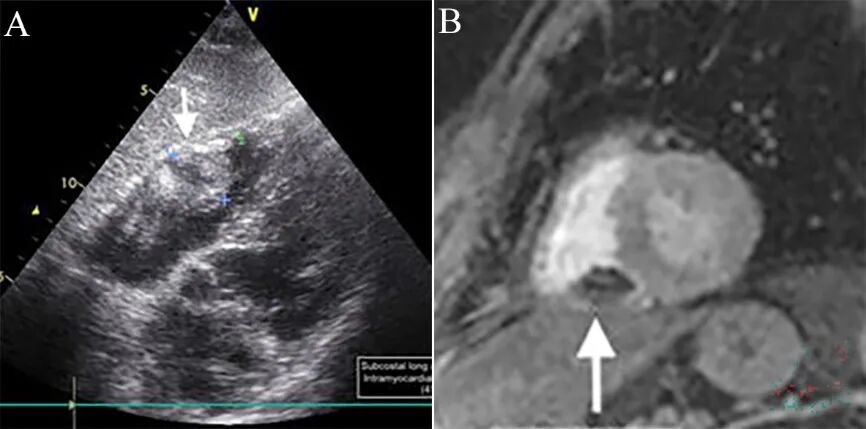

图2 CMR表现[1]。

急性下壁心肌梗死PCI顺利开通右冠,术后12小时出现胸痛和下壁导联ST段抬高,伴cTnT再次升高,但再次冠造未见血管堵塞和穿孔。随后数天症状缓解,cTnT逐渐降低,但下壁导联持续性ST段抬高,心超随访发现右室壁内血肿 (41×29 mm) (A,箭头),心脏MR证实右室下壁夹层血肿(B,箭头)。